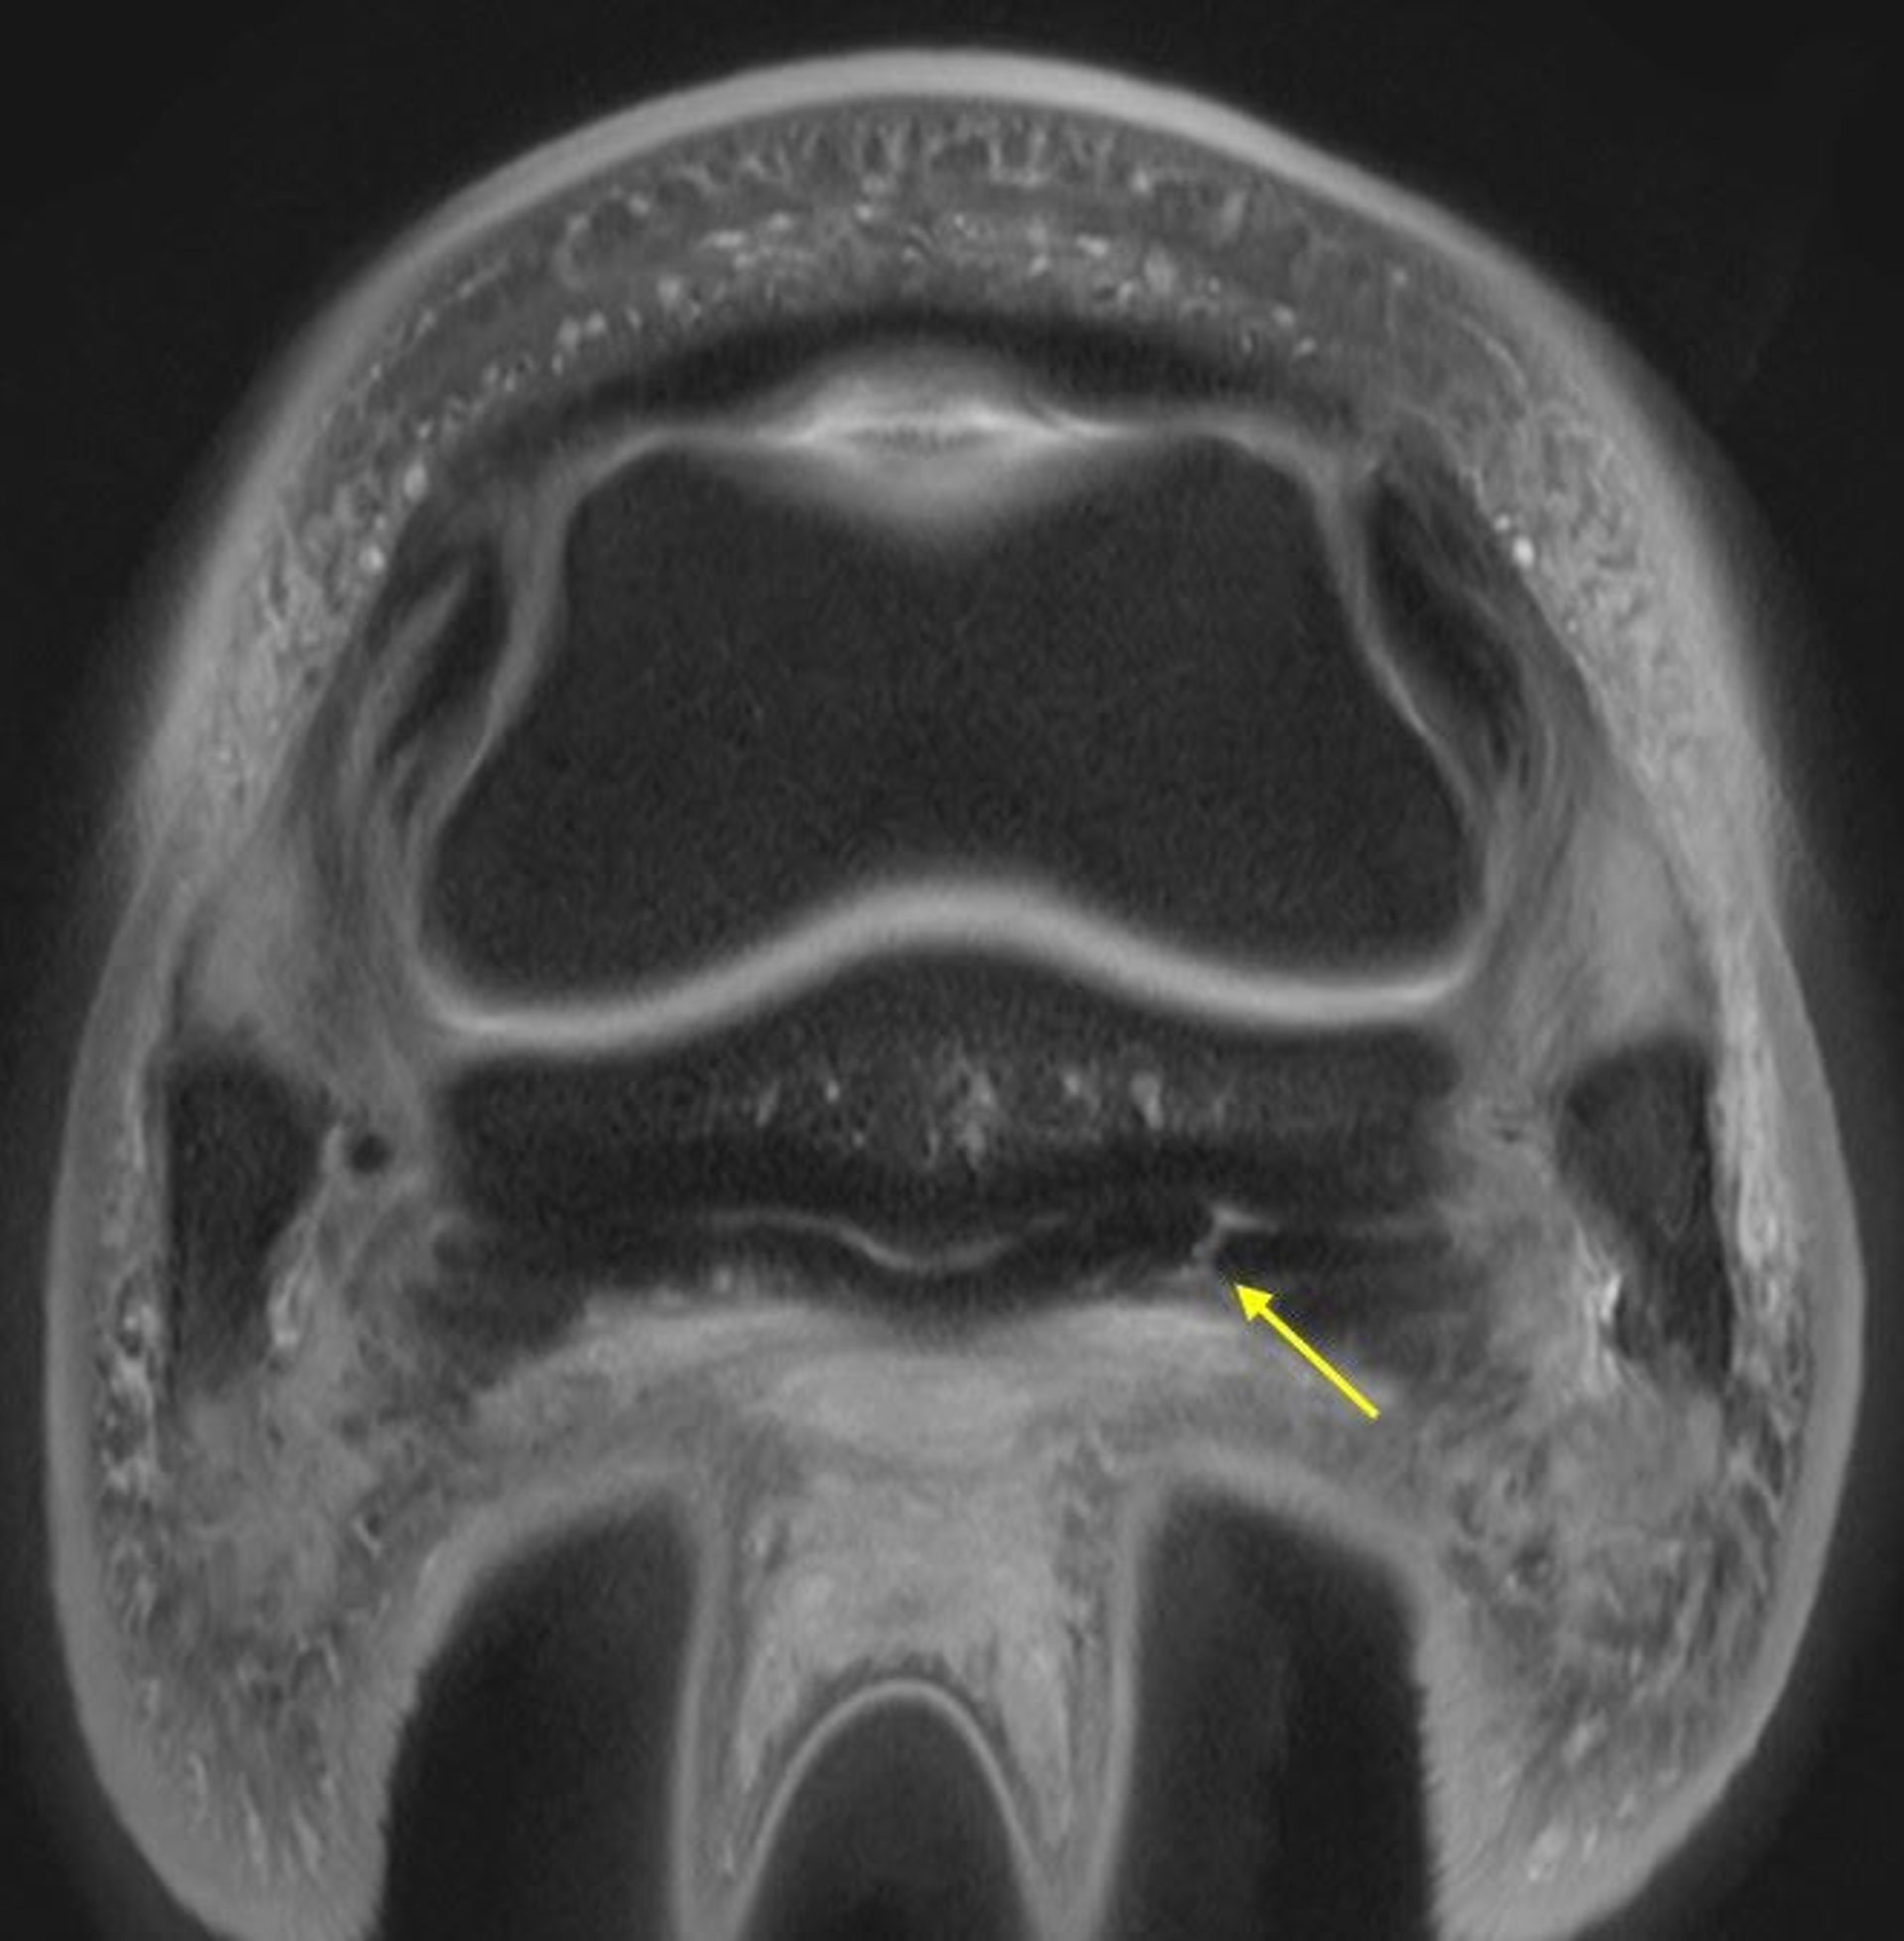

Deep digital flexor tendon (DDFT) injuries are more common within compressed regions of the limb, such as overlying the palmar fetlock joint and proximal palmar border of the navicular bone (see DDFT linear tear image).

Advanced imaging modalities such as MRI are beneficial for diagnosis of DDFT lesions within the hoof capsule and at the proximal metacarpal/metatarsal regions.